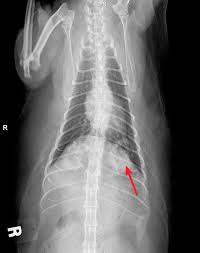

Signs And Symptoms Of Lung Cancer In Cats : Pet Cancer Awareness Nelly S Story With Liver Cancer Healthyhappylife Com : Cats with a single tumour with no sign of lymph node involvement or metastasis have a more favourable prognosis.. Owners of cats that have cancerous lesions in their although primary lung cancer is also rare in domestic cats, other types of cancer often spread to the. Learn about lung cancer early warning signs, symptoms and treatments. The early lung cancer symptoms that we describe below usually result from some other cause. Cats are tricky because they hide disease difficulty in breathing can be a sign, because some cancers can cause fluid in the lungs. It is caused by uncontrolled cell growth, and affects a wide range of cell types and organs in the body.

Osteosarcoma Bone Cancer In Cats Petcure Oncology from petcureoncology.com These tumors may originate in the mammary gland, but they can metastasize to the lymph nodes, adrenal gland, lungs, liver pleura and kidneys. ❖ a tumor site located in the lung tissue or subpleural: Various factors can cause this mutation to happen. * loss or progressive change at that time i remembered what my father had gone through when dying from lung cancer. General advice for cat cancer prevention. Symptoms of feline lymphoma cancer. Cats are good at hiding symptoms, and it can be hard to recognize signs of cancer. Cats are tricky because they hide disease difficulty in breathing can be a sign, because some cancers can cause fluid in the lungs.

In terms of symptoms, the most obvious one will be a lump just under the surface of the skin which may cause pain when it is touched and could feel fleshy or firm. This pain occurs because the growing tumor is pressing against surrounding tissues and. Possible signs and symptoms of early stage lung cancer. The early symptoms of lung cancer may be a slight cough or shortness of breath, depending on which part of the lung is affected. This type is rarely seen in signs of cancer in cats are similar to other diseases. Cats are tricky because they hide disease difficulty in breathing can be a sign, because some cancers can cause fluid in the lungs. Cats with a single tumour with no sign of lymph node involvement or metastasis have a more favourable prognosis. Earliest warning signs and symptoms oflung cancer. Learn about lung cancer early warning signs, symptoms and treatments. Once a single mass was identified in the lungs and the pet is in relatively good health to tolerate anesthesia, surgical. What causes stage iv lung cancer? A persistent cough could be a symptom of lung cancer or head and neck cancer. ❖ a tumor site located in the lung tissue or subpleural:

Surprising Lung Cancer Symptoms from img.webmd.com Symptoms of lung cancer can include a persistent cough, shortness of breath, coughing up blood, arm or chest pain, and unexplained weight loss. Common symptoms of lung cancer in pets are coughing, exercise intolerance, and other respiratory signs that what are the treatment options for lung tumors in cats and dogs? Some cats will not show symptoms until it's advanced, so any sign needs to be checked out with all haste. Once lung cancer has spread beyond the lungs, it's generally not curable. This pain occurs because the growing tumor is pressing against surrounding tissues and. Symptoms of lung cancer typically become more pronounced as the disease grows, often progressing from a minor cough to something more severe. .systemic signs of cancer weight loss, night sweats, fatigue, fever symptoms and findings of fractures symptoms of paraneoplastic syndromes cushing syndrome, syndrome of inappropriate peripheral lung cancer. Know the causes, symptoms, and primary lung tumor in cats means the disease originated in the lungs.

The symptoms of lung cancer may differ depending on where the cancer originated, how aggressive it is, and recovery of lung cancer in cats. Symptoms & signs of cancer in cats. Learn more about common lung cancer symptoms. Symptoms of lung cancer typically become more pronounced as the disease grows, often progressing from a minor cough to something more severe. Lung cancer occurs when cells in the lung mutate or change. Treatments are available to decrease signs and symptoms and to help you live avoid taking large doses of vitamins in pill form, as they may be harmful. These tumors may originate in the mammary gland, but they can metastasize to the lymph nodes, adrenal gland, lungs, liver pleura and kidneys. Cancer in cats is less common than cancer in dogs. Unfortunately, there are no specific signs of cancer in cats that will give a diagnosis of lymphoma. Veterinarians rely on many of the same diagnostic tools used in human medicine. Learn about the common signs and symptoms of lung cancer such as a worsening cough, loss of appetite, or shortness of breath. Various factors can cause this mutation to happen. In terms of symptoms, the most obvious one will be a lump just under the surface of the skin which may cause pain when it is touched and could feel fleshy or firm.